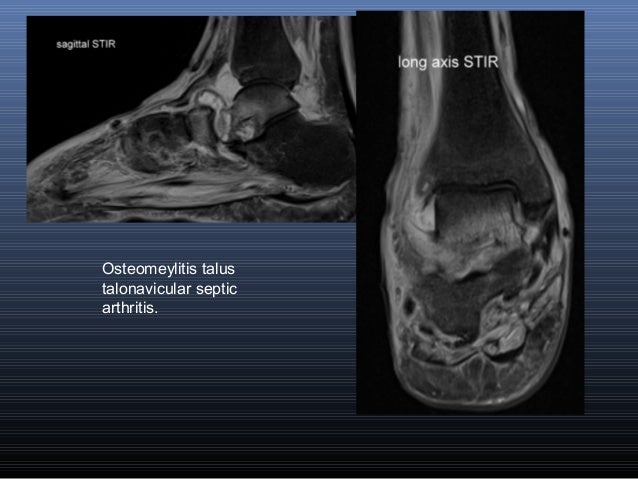

Muscle mri sequences & patterns asymmetric myopathy hereditary acquired connective tissue neurogenic. Muscles of the ankle and foot. This is the first of two parts on the intrinsic muscles of the foot. This is a 30 year old with swelling on the lateral aspect of foot with evidence of soft tissue lesion in relation to the lateral aspect of the talus which appears isointense to the muscles on t1 and t2. Bone contusions, osteonecrosis, marrow oedema syndromes, and stress > fractures) > synovial based disorders ( e.g.